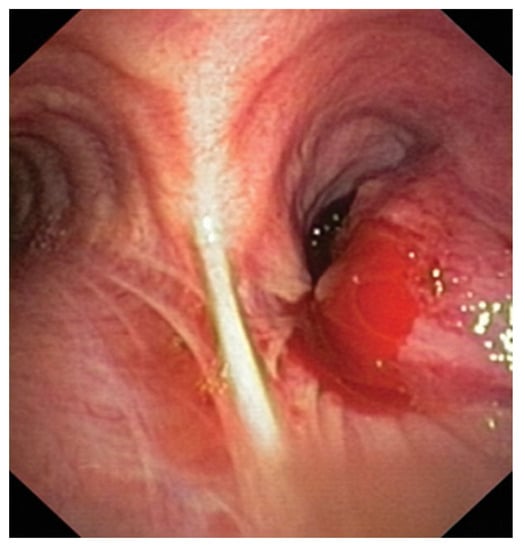

2.3. Endobronchial Ultrasound (EBUS) Transbronchial Needle Aspiration

RP-EBUS-GS—Guided Endobronchial Ultrasound in the Era of Molecular Testing of Tumor Tissue